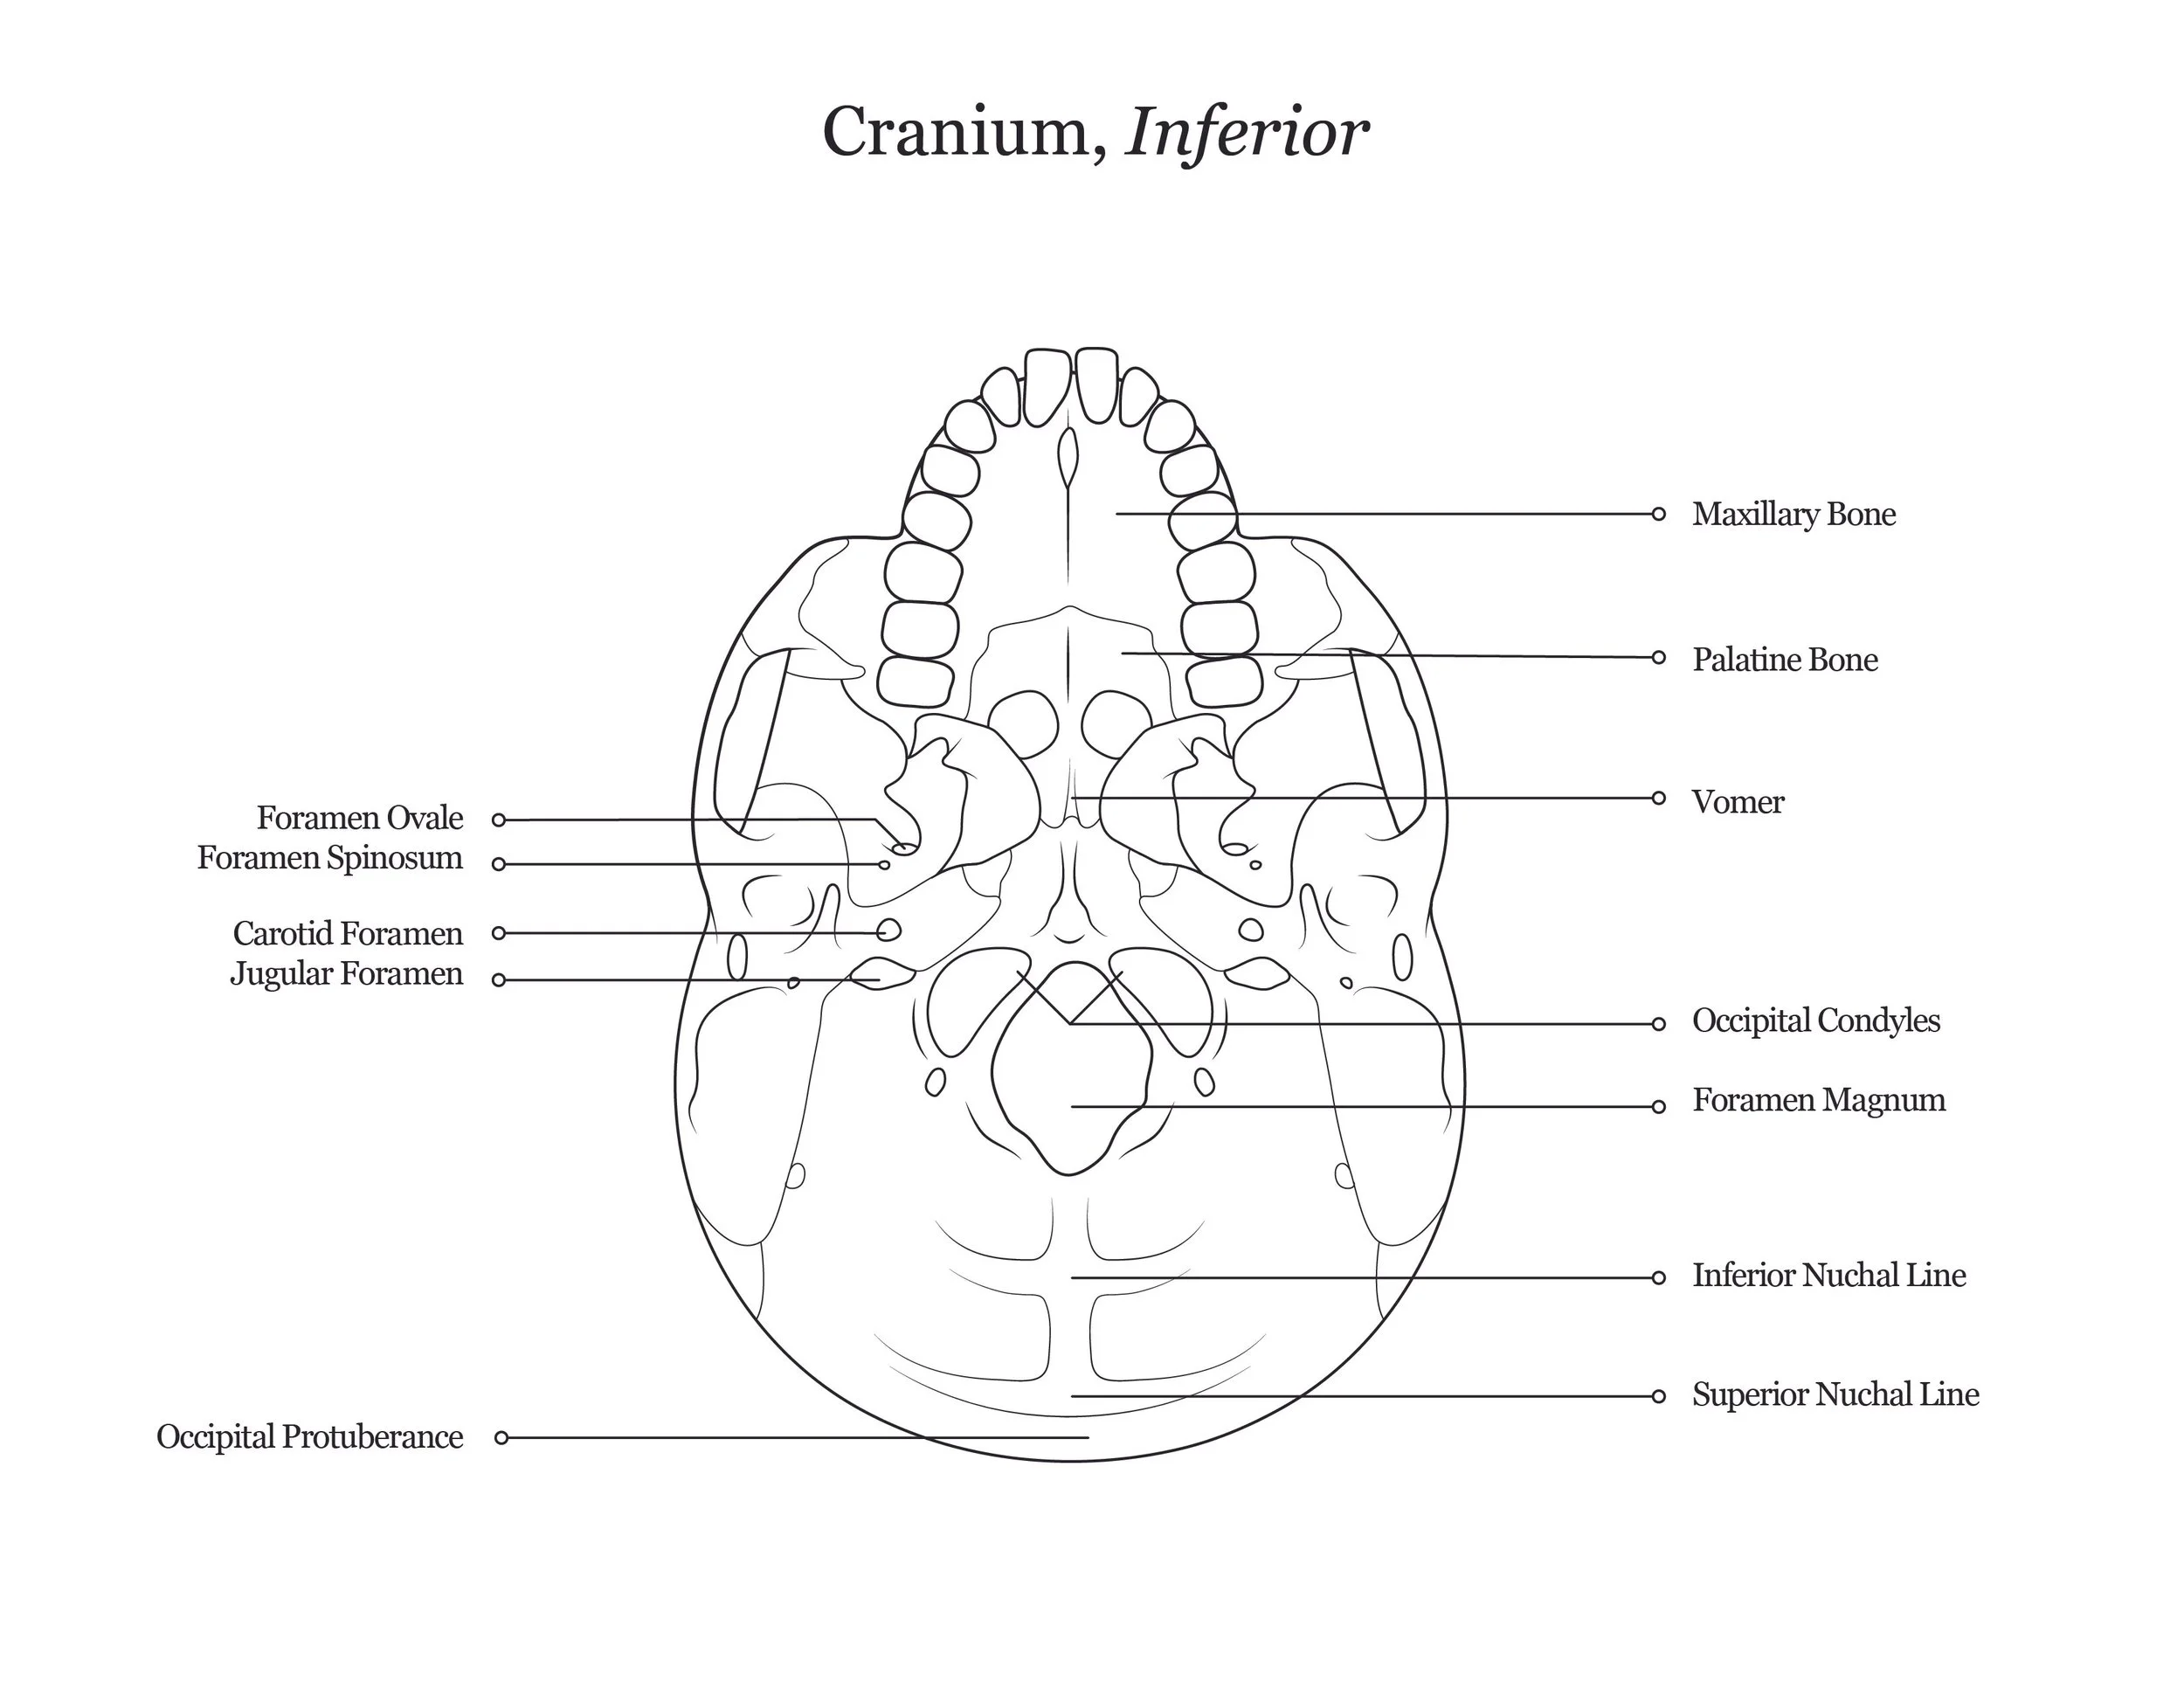

A series of anatomical illustrations created for Arcadia University’s Biology Department.

This project involved illustrating a series of diagrams for a cat dissection manual, focusing on skeletal and muscular anatomy. I consolidated multiple reference sources and firsthand specimen observation into a cohesive visual system for instructional use. Illustrations were refined iteratively to ensure anatomical accuracy, consistency, and clarity for students.